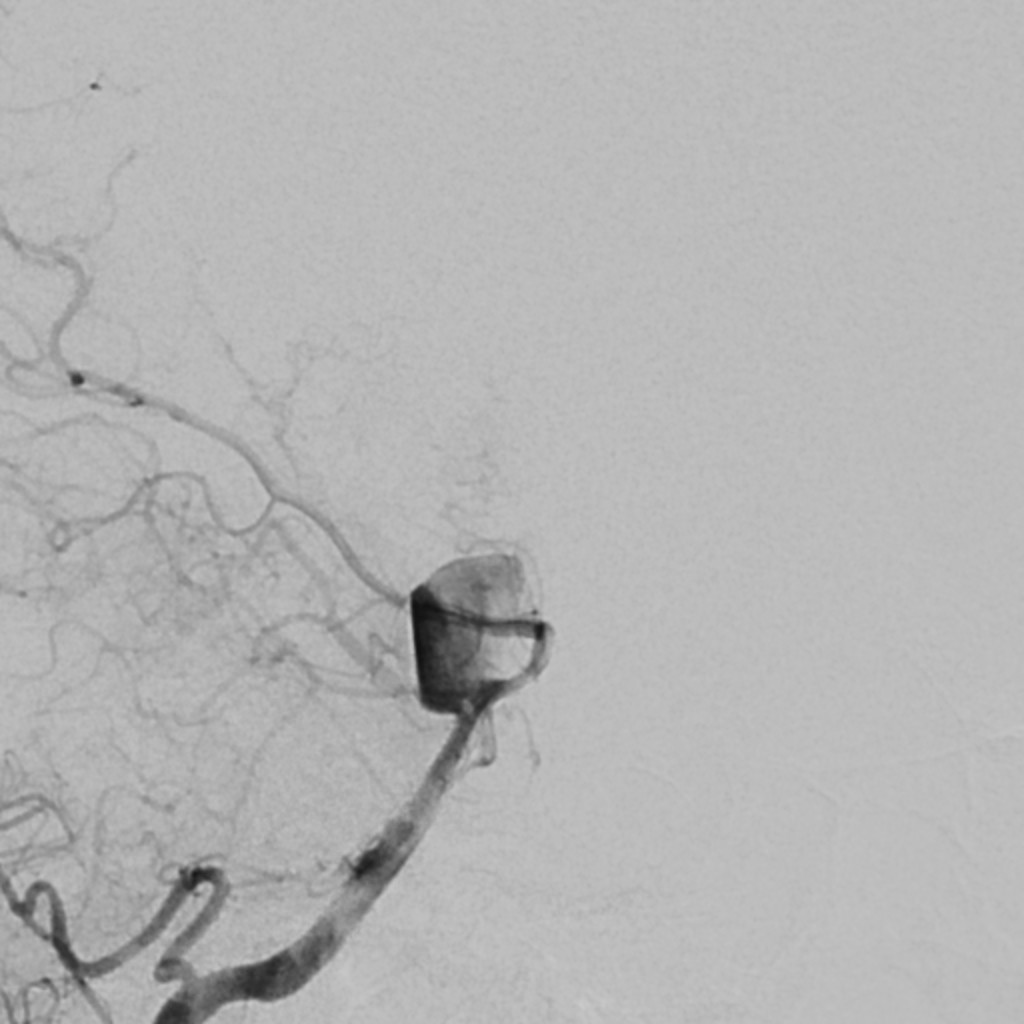

Šta je mehanička trombektomija?

Minimalno invazivan postupak kojim se fizički uklanja krvni ugrušak iz arterije u mozgu.

Zašto je vreme ključno?

U prvih 6h prijema moguć je oporavak od 50% a u prvih 3h i do 80%.